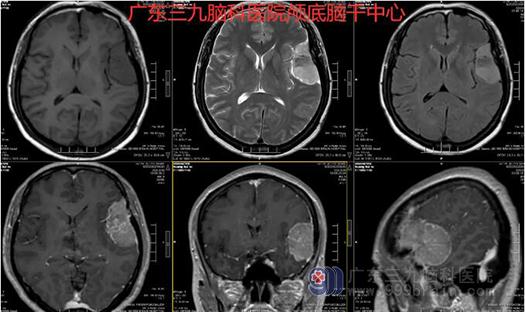

图2:术前MR示左侧额颞顶骨内板下示一团块状占位性病变,边界清,大小约54mm×53mm×28mm,呈稍长T1长T2、FLAIR序列高信号影,间杂斑片状不匀偏等T1短T2、FLAIR序列低信号影,增强后病变呈明显强化,强化不均匀,邻近硬脑膜轻度增厚呈线样强化;病变周围示脑脊液环,邻近左侧额颞岛叶受压移位,左侧颞叶并示斑片状稍长T1长T2、FLAIR序列高信号影。邻近左侧侧脑室轻度受压变窄,脑沟变浅